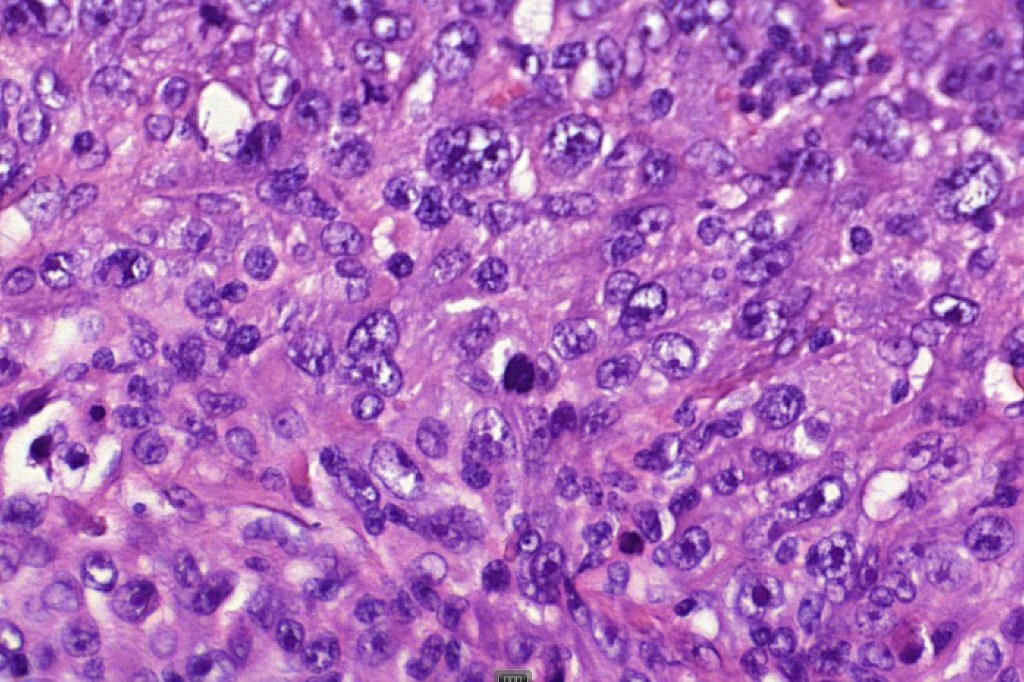

These are very rare variants of amelanotic or virtually amelanotic melanoma where a primary melanoma or a metastasis shows partial (DN) or complete loss (UN) of recognizable histological and immunohistochemical features. The histology may lead the pathologists to consider lymphoma, sarcoma, anaplastic carcinoma or a small cell tumor. Some examples of rhabdoid melanoma & melanoma with heterologous differentiation probably belong in this category. Ultimately, if there is no identifiable/recognizable primary tumor, diagnosis may only be comfortably made with next-generation sequencing. In the cases presented below, immunohistochemistry was of value in determining the melanoctic nature of the tumor (undifferentiated melanoma).